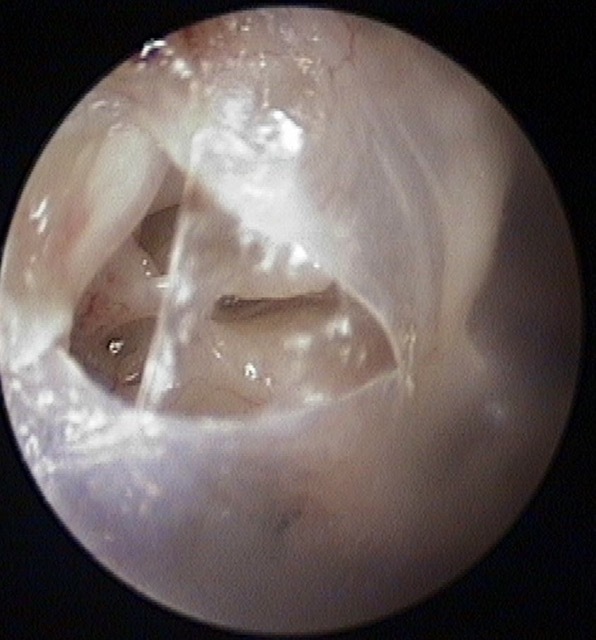

Perforation